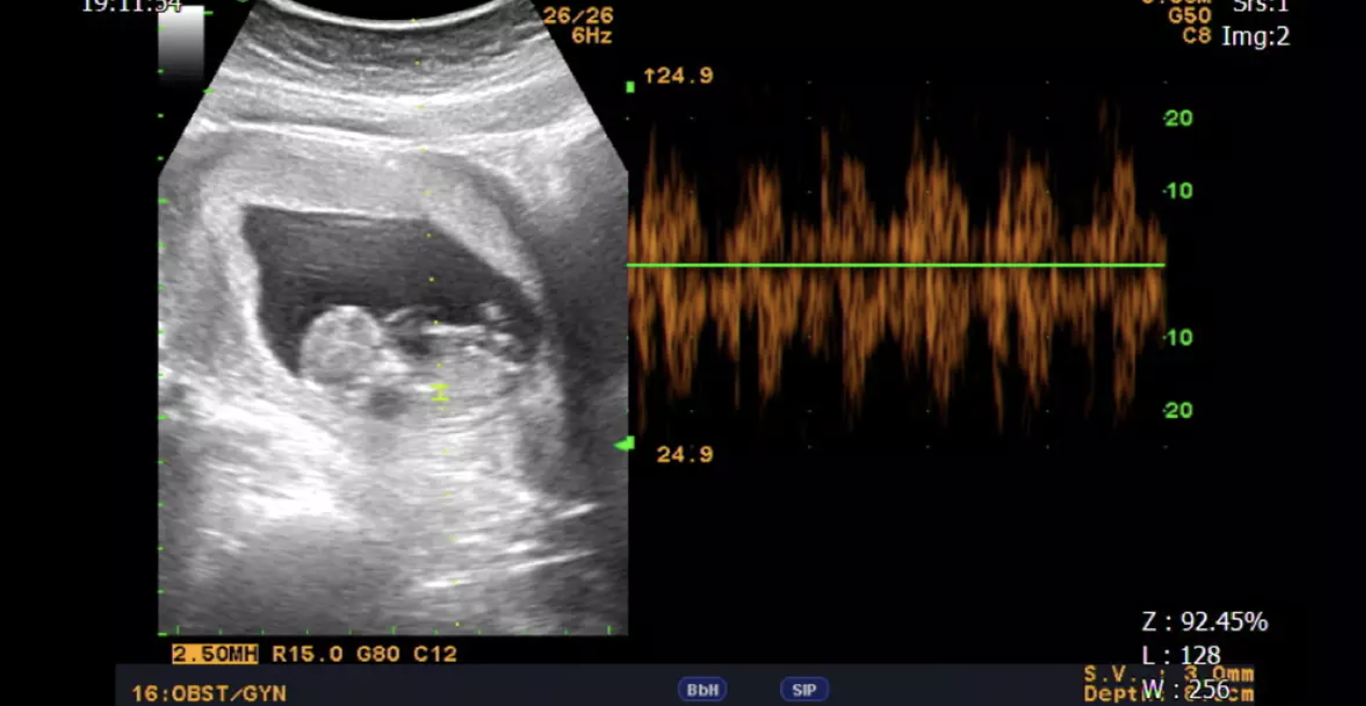

中山醫學大學附設醫院生殖醫學中心致力提供完善且可靠的專業服務。診斷方面擁有多項技術,包括荷爾蒙卵巢功能抽血檢驗、同房試驗、精密的電腦輔助精液分析、進階版精蟲功能測試、子宮鏡、腹腔鏡、胚胎著床前基因診斷及子宮內膜容受性檢查等。這些技術讓我們能提供在試管嬰兒上一條龍的服務,同時也專注於試管嬰兒、人工授精、凍卵、一般婦科、婦科腫瘤及腹腔鏡、多囊性卵巢、子宮肌瘤、子宮肌腺症、子宮內膜異位症等專業診療領域。